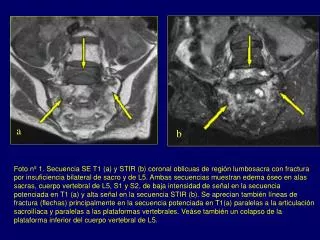

1. a b Foto nº 1. Secuencia SE T1 (a) y STIR (b) coronal oblicuas de región lumbosacra con fractura por insuficiencia bilateral de sacro y de L5. Ambas secuencias muestran edema óseo en alas sacras, cuerpo vertebral de L5, S1 y S2, de baja intensidad de señal en la secuencia potenciada en T1 (a) y alta señal en la secuencia STIR (b). Se aprecian también líneas de fractura (flechas) principalmente en la secuencia potenciada en T1(a) paralelas a la articulación sacroilíaca y paralelas a las plataformas vertebrales. Veáse también un colapso de la plataforma inferior del cuerpo vertebral de L5.